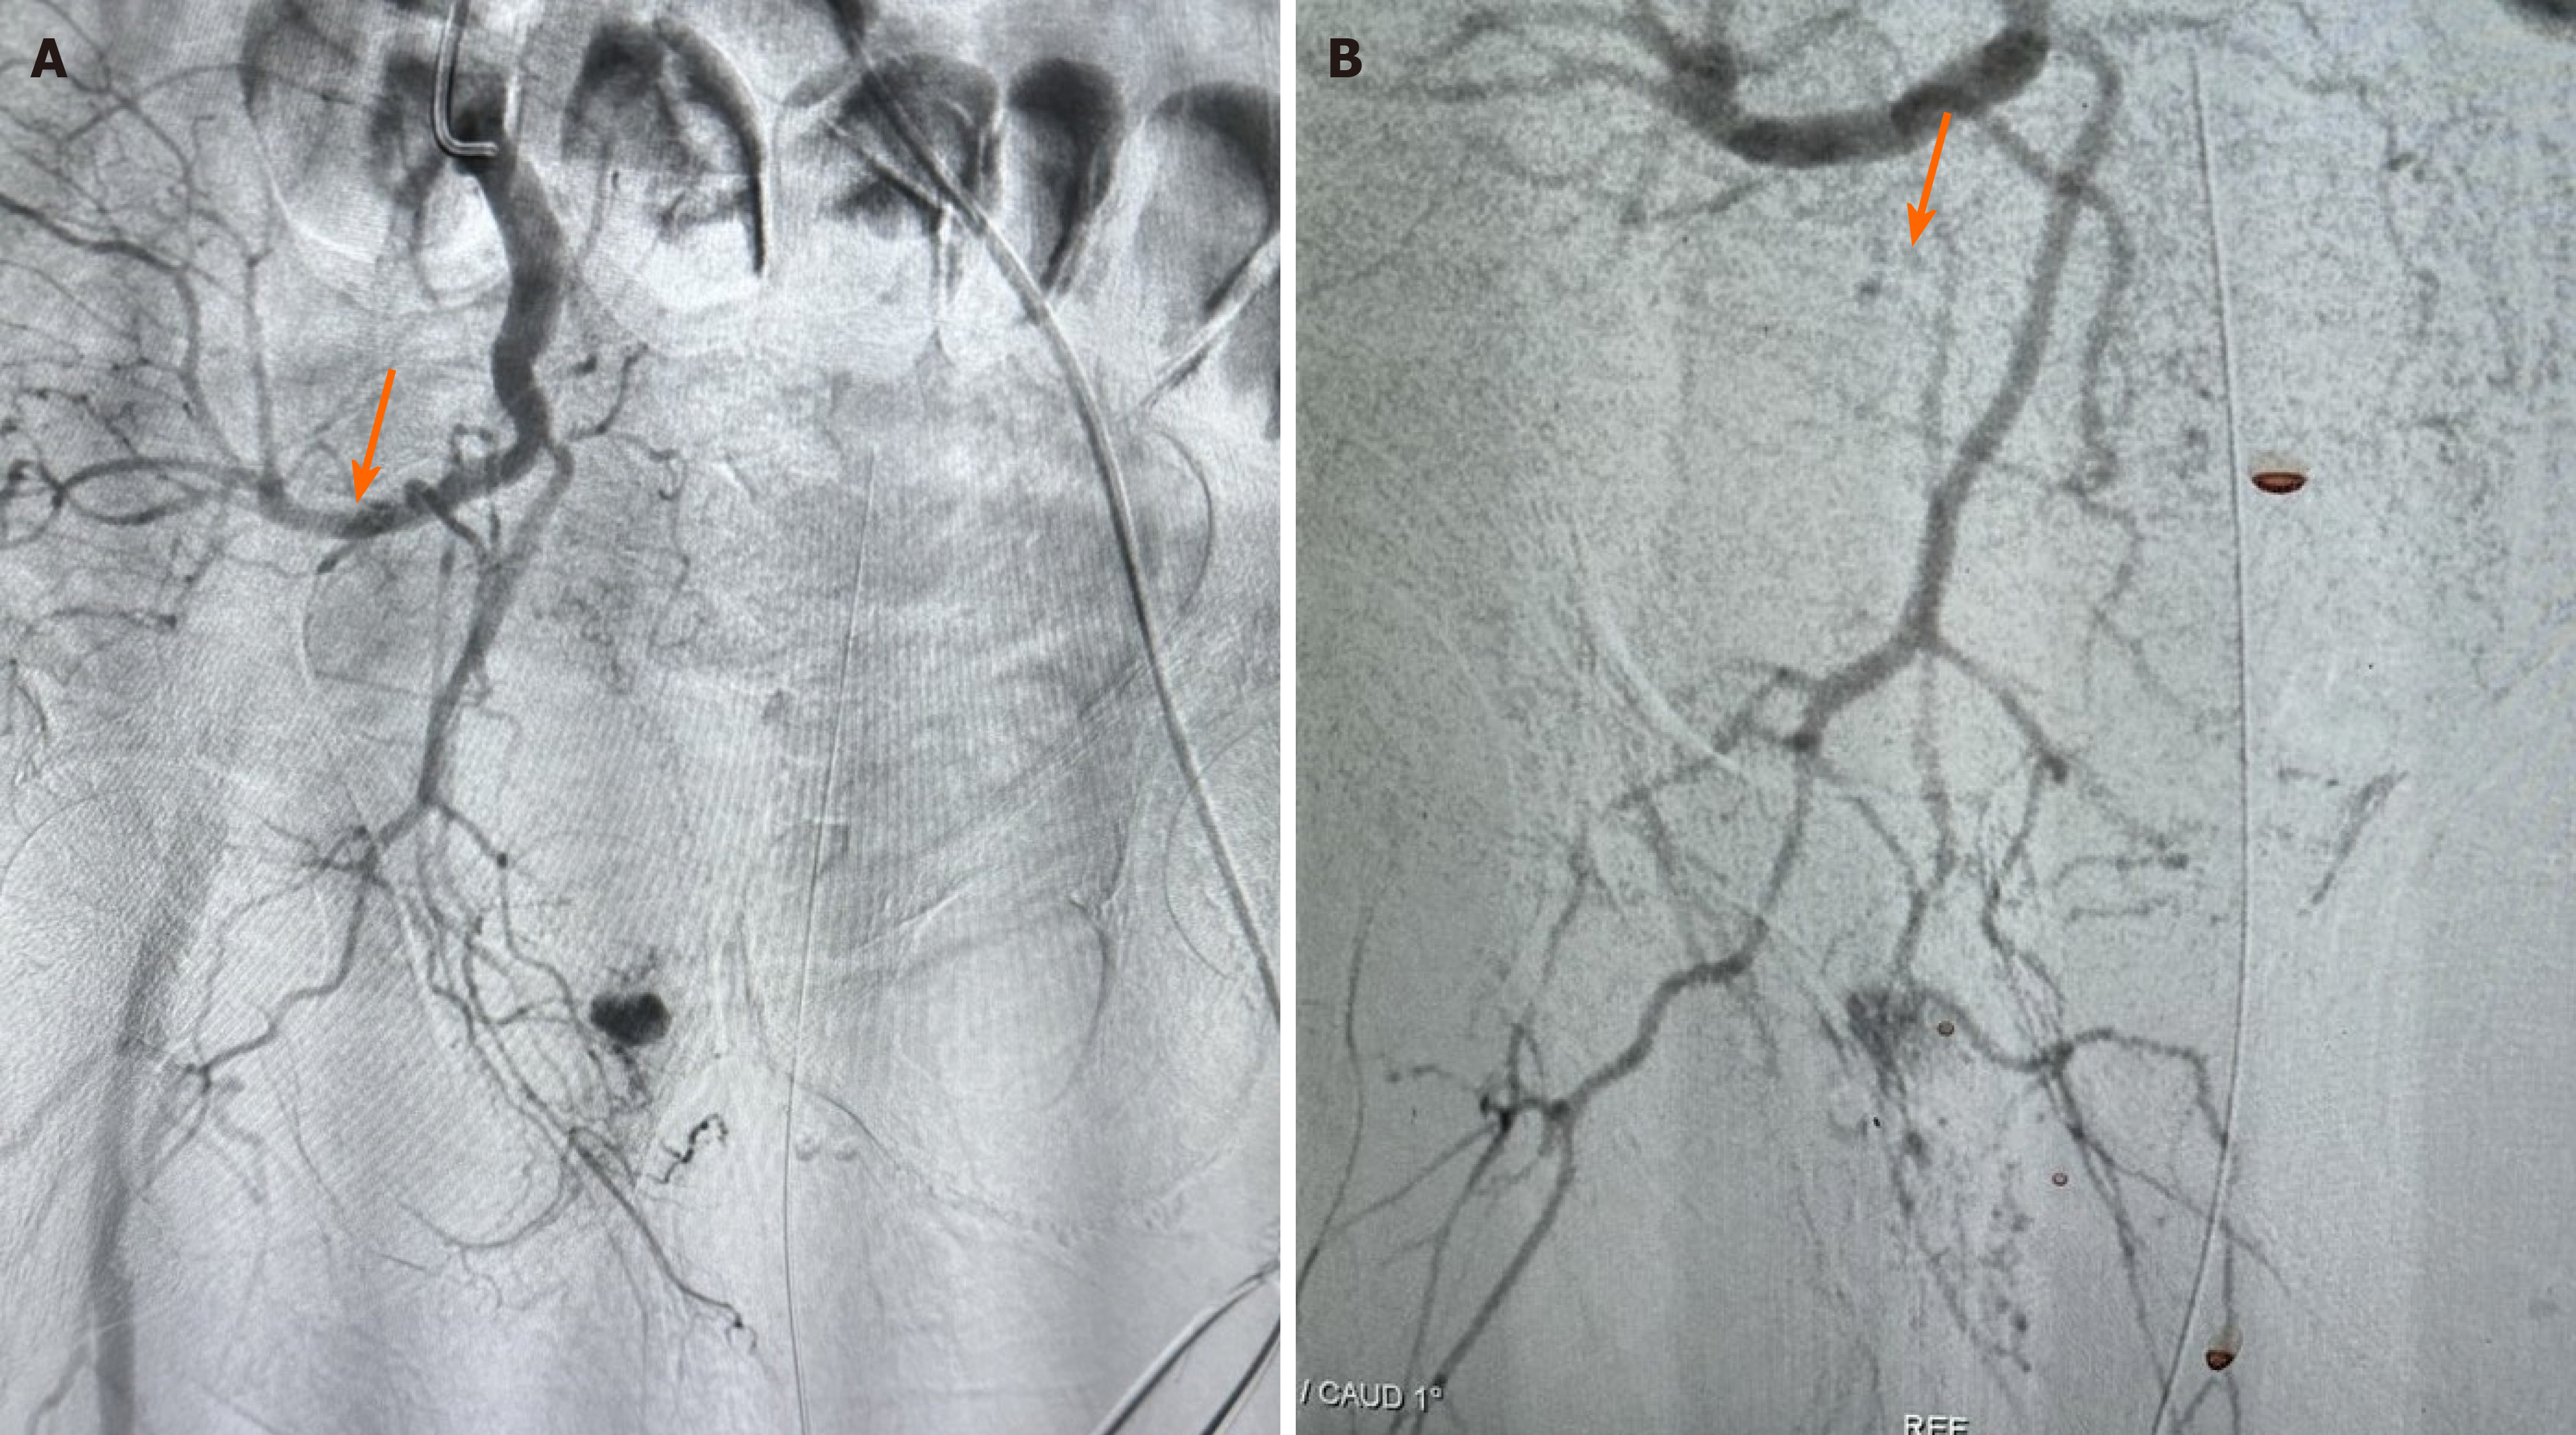

The digital subtraction angiography revealed active bleeding from a branch of the medial femoral artery (Figure 3A). The lost blood was accumulated chiefly around the area of piriformis, gemellus superior, gemellus inferior and obturatorius externus muscles. Emergency embolization of the bleeding artery was performed to stabilize the patient (Figure 3B). Liquid glue was utilized as embolic agent. Following the embolization, the patient’s vital signs stabilized and the BUN and creatinine concentrates normalized. LMWH treatment was reinstated four days after the embolization. Intensive monitoring continued in the hospital for a total of 15 days for continuous monitoring, mobilization by physiotherapists and antibiotic medication for a respiratory infection he developed.